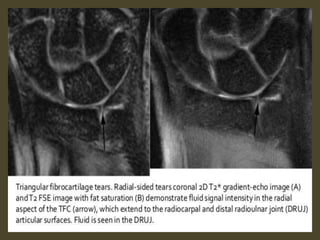

Triangular fibrocartilage complex tear.

Acute TFCC tear on FS T2-WI (A) and T1-WI (B).

TFCC 1B tear (arrow) on coronal T1-WI (B) and coronal FS T2-WI (C).